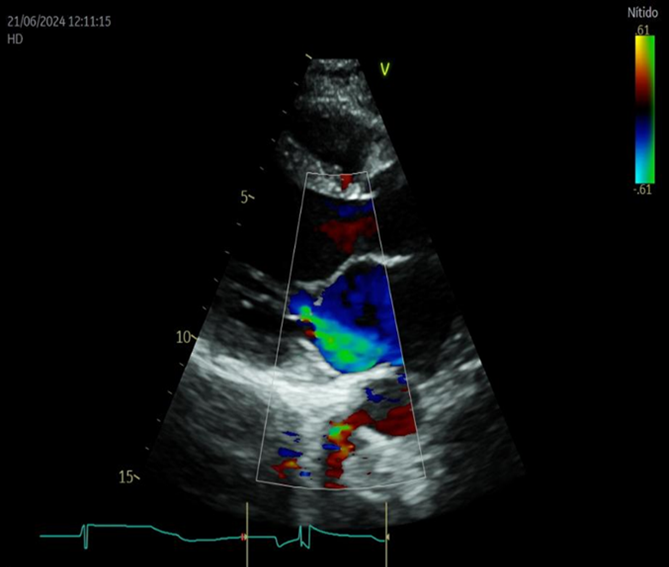

Caso clínico: reportamos el caso de una paciente de 31 años portadora de miocardiopatía dilatada, con fracción de eyección del ventrículo izquierdo por ecocardiograma de 38%, que cursó embarazo gemelar de alto riesgo.

Discusión: las embarazadas con miocardiopatía dilatada y fracción de eyección del ventrículo izquierdo descendida, tienen mayor riesgo de complicaciones, como insuficiencia cardíaca, edema agudo de pulmón, arritmias potencialmente peligrosas, muerte súbita, parto prematuro, muerte fetal. En el embarazo gemelar, el riesgo se incrementa, debido al mayor aumento del volumen sanguíneo y la demanda adicional sobre el corazón.